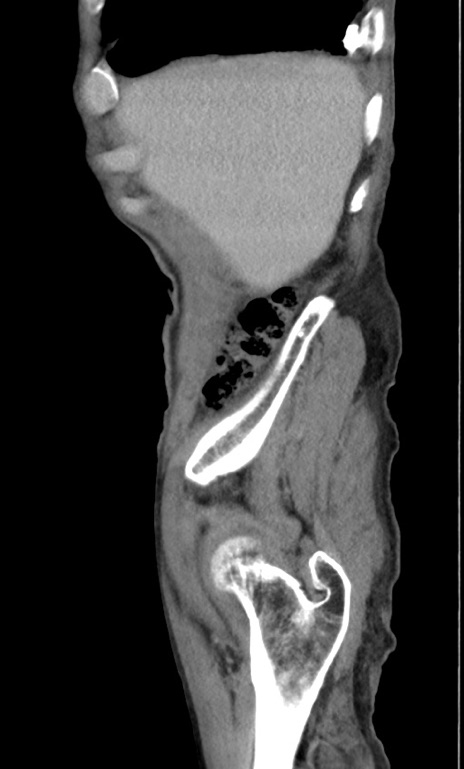

症例3(矢状断像)

【症例】 70歳代男性

【主訴】右鼠径部腫瘤、疼痛

【現病歴】本日朝より上記主訴あり、受診。

【既往歴】膀胱癌にて膀胱全摘、両側尿管皮膚瘻

【データ】WBC 5600、CRP 0.56